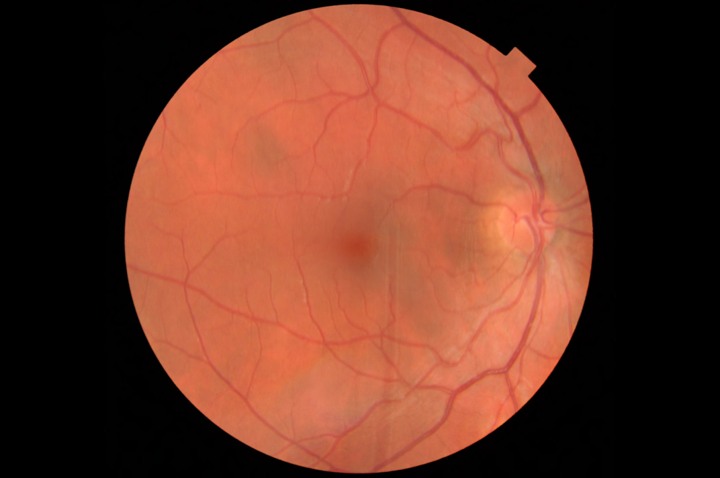

A 3D section of the layers ofthe retina and vitreous jellyA 3D section of the layers of the retina and vitreous jellyAge-related Macular Degeneration Dry FormAge-related Macular Degeneration Dry FormAge-related Macular Degeneration Wet FormAge-related Macular Degeneration Wet FormThe vitreous (jelly) pulling on the retinaThe vitreous (jelly) pulling on the retinaImage of Retina (back of the eye)Image of Retina (back of the eye)